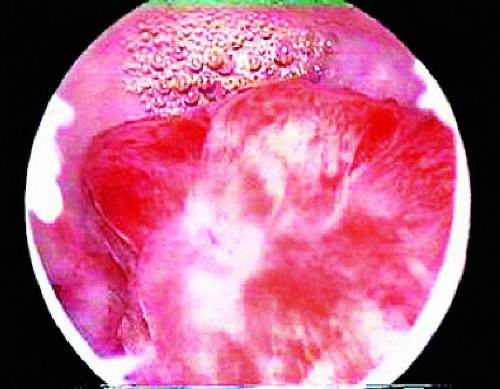

Аденоматозный полип

Одним из предраковых заболеваний толстой кишки является аденоматозный полип. Он представляет собой полип, который растет на поверхности толстой кишки и имеет большой риск перерождения в рак.

Полипы в организме возникают в связи с нарушением регенераторного процесса в слизистой оболочке. Аденоматозные полипы - это неопластические новообразования, которые формируются из диспластического эпителия, который в нормальном состоянии в желудке отсутствует.

Есть 3 типа аденоматозных полипов:

1. Трубчатые аденомы. Возникают в любом месте толстой кишки.

2. Трубчато-ворсинчатые аденомы. Могут вырасти в толстой кишке, других отделах желудочно-кишечного тракта или в любой части тела.

3. Ворсинчатые аденомы. Чаще встречаются на поверхности прямой кишки.